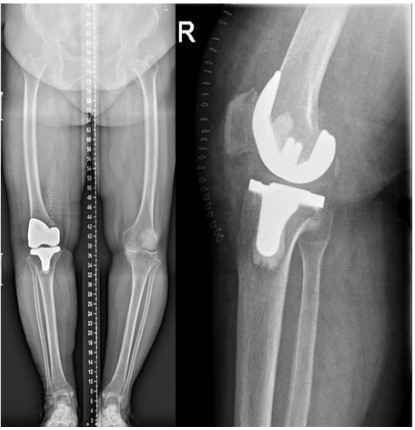

The patient came back again to the hospital 4 months following TKR, and complained of pain in her right hip for a month. Clinical examination and X-ray film: show the diagnosis of fracture of the right femoral neck, The patient denied any traumas (Figure 3).

Figure 3: Case 1 fracture of the right femoral neck

The patient returned again nearly one year later, and complained of pain in her left hip for 20 days, especially during movement. Clinical examination and X-ray film; made the diagnosis of fracture of the left femoral neck. Also, the patient did not suffer any trauma (Figure 7).

Figure 7: Case 2 fracture of the left femoral neck

The interval between femoral neck fractures after TKR was 2 to 17 months, with an average of 8 months (4 and 12 months in our two cases, respectively). Amite Pankaj [11] proposed that early X-ray examination sometimes fails to detect femoral neck fracture, and safer MRI can provide earlier diagnosis. The early diagnosis is important, because it helps to the conservative treatment and avoid the shifting after the fracture, thus avoiding surgical treatment [2,8,10]. In our case, both patients experienced pain in the groin and presented to the doctor 1 month later. The patients did not pay much attention to these symptoms. Therefore, this complication should be highly suspected when ipsilateral hip pain occurs after TKR, especially in patients with poor mobility or obvious osteoporosis.